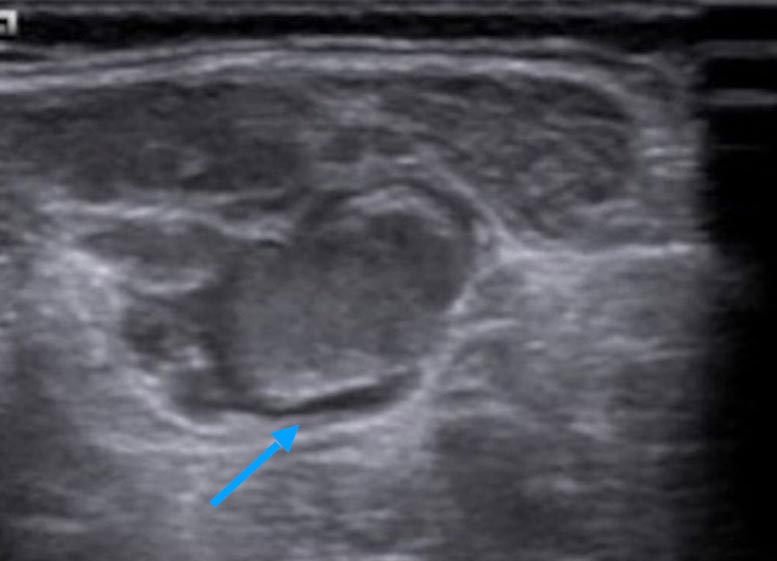

If imaging is ever necessary, sonography is the first choice. Thrombophlebitis is easily visualized within the anechoic venous malformation components as echogenic, non-compressible circumscribed foci.

On sonography, a normal vein or venous malformation is soft and readily compressible with the transducer. The non-clotted blood is virtually anechoic (black), and slow blood flow is detectable on color-coded duplex sonography.

As the blood clot matures with time, it becomes more echogenic sonographically, making it easy to distinguish from anechoic blood. Often starting at the edge, i.e., at the vessel wall, there is a slow recanalization of the involved vessel. This is visible as anechoic fluid around the echogenic thrombus.

In ultrasound elastography, thrombi tend to be harder than the surrounding tissue. Therefore they are also relatively easy to detect according to the color scaling setting.